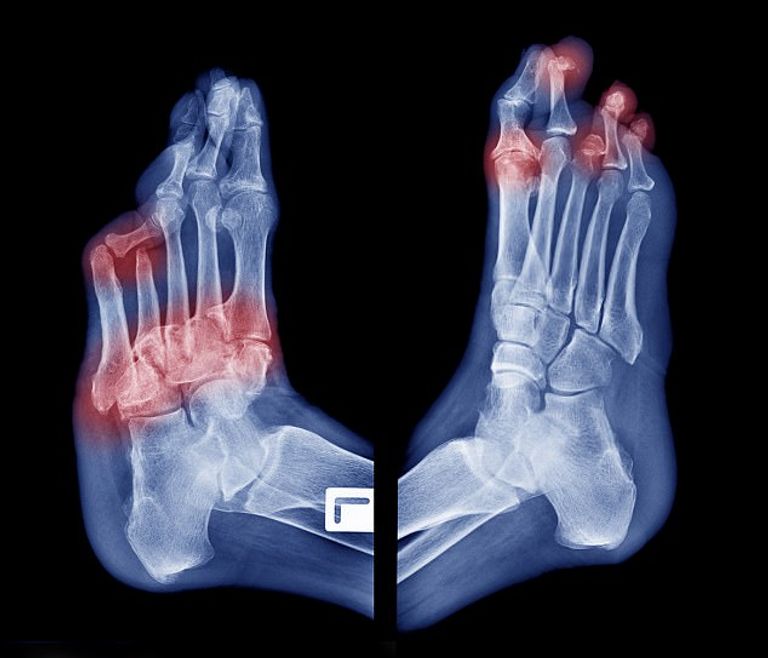

وأوضحت الشركة المنتجة أن البساط به مجسات لقياس درجة الحرارة والالتهابات التي تكشف التقرحات تحت الجلد، وتحدث التقرحات عندما يقل معدل جريان الدم ويقل معدل الأكسجين الذي يحتاجه الجلد، ما يزيد خطر الإصابة بها، خاصة تلك التي لا تشفى.

وأضافت أن هذا الجهاز يمكن أن يساعد الملايين من مرضى السكري الذين يتهددهم خطر البتر مع ضعف الدورة الدموية في أقدامهم وارتفاع السكري في الجسم. وتحتاج ٤٠٪ من تقرحات السكري لـ٣ أشهر على الأقل حتى تشفى ولا تلتئم أكثر من ١٤٪ منها.